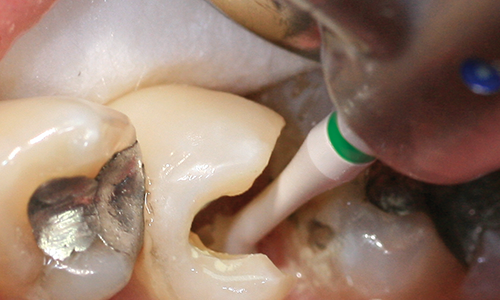

The CeraBur® is a ceramic round bur used for controlled, intuitive excavating. It allows you to feel when the instrument leaves decayed dentin, saving more healthy tooth structure. The CeraBur® also eliminates the need for explorers and spoons for evaluating decay removal.

Its slim neck and white working part allows it to stand out against the brownish shade of the carious dentin.